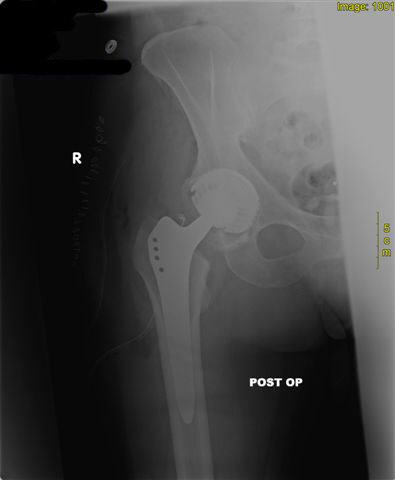

| postoperatives Zustand mit Zementfrei implantierter Hüfttotal-Endoprothese |